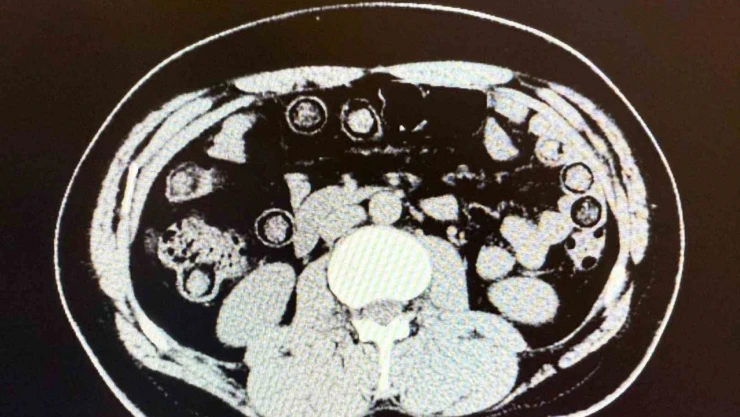

Muş Valiliği tarafından yapılan açıklamada, “Narkotik Suçlarla Mücadele Şube Müdürlüğümüzce uyuşturucu madde sevkiyatına engel olmak için yapılan çalışmalar neticesinde İran uyruklu 2 şahsın şehirlerarası yolcu otobüsü ile illere uyuşturucu madde nakli gerçekleştirebilecekleri değerlendirilmiş, 6 Aralık günü saat 11.30 sıralarında şüpheli şahısların görevlilerimizce yapılan sorgulamasında uyuşturucu madde naklettikleri yönünde kuvvetli şüphe oluşmuştur. Hastanede yapılan iç beden muayeneleri sırasında çekilen tomografi görüntülerine göre uyuşturucu madde yuttukları tespit edilmiştir. Hastanede yapılan tespit sonrasında şahısların midelerinde toplam 94 adet kapsül içerisinde daralı ağırlıkları 928 gram gelen metamfetamin maddesi ele geçirilmiştir. Şüpheli şahıslar hakkında ‘uyuşturucu ve uyarıcı madde ticareti’ suçundan işlem yapılmak üzere Cumhuriyet Başsavcılığına intikal ettirilmiş ve çıkarıldıkları mahkemece tutuklanmışlardır” denildi.